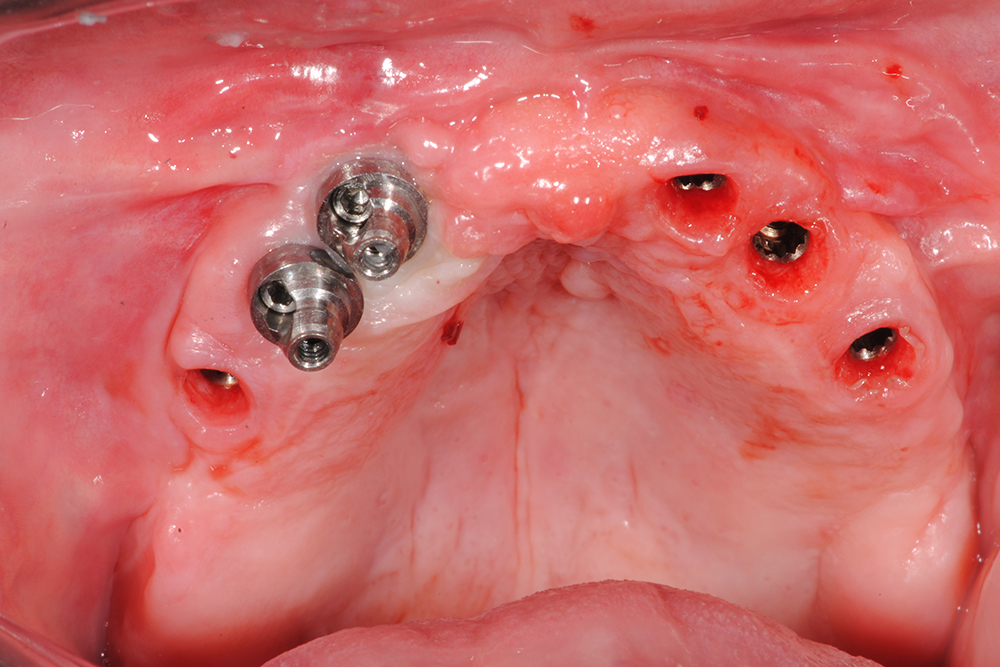

Ripristino dell'arcata superiore ed inferiore su impianti con ricostruzione estetica in zirconia e ceramica Category: Lavori ImpiantiMaggio 9, 2018Condividi questo ProgettoShare with FacebookShare with TwitterShare with Google+Share with PinterestShare with LinkedInProject navigationPreviousPrevious project:Ripristino dell’arcata superiore atroficaNextNext project:Protesi mobile superiore + Overdenture inferiore